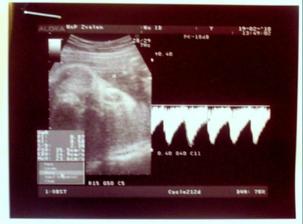

- 19.2.10 sono v 30tt , pani doktorka nas pozrela od hlavy po paty a vsetko je tak ako ma, skontrolovala aj prietoky a su na vybornu a vazime 1670g a

mame na 100% potvrdene DIEVČATKO 🙂.....